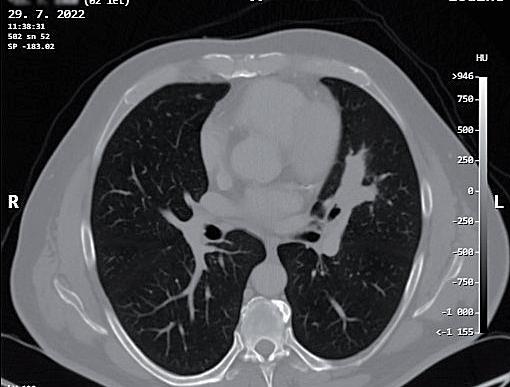

obr. 3.4 Adenokarcinom plicní po neoadjuvanci indikovaný k operačnímu řešení u 65letého muže na CT (a) a PET CT (b) obraze je masou nádoru natolik objemný (v největším rozměru prakticky 10 cm), že postihuje více než objem jednoho segmentu horního laloku levé plíce. Pro bezpečné vyjmutí resekátu nádoru, laloku plicního, je v tomto případě nutná regulérní torakotomie. Nádor dosahuje blízkosti odstupu tepenných větví pro horní lalok. Takový nález není vhodný pro videoskopické řešení. Výkon z torakotomie v takových případech upřednostníme. Po otevřené horní lobektomii vlevo a kompletní spádové lymfadenektomii nebylo patologem u pacienta nalezeno žádné nádorové postižení uzlin

uzlinách. Indikující chirurg je však často v situaci, kdy se primární ložisko v plíci podezřelé z maligního původu nezdařilo verifikovat bronchoskopií s biopsií nebo kar táčkovou cytologií, ani punkční transparietální biopsií pod CT (obr. 3.9, 3.10).